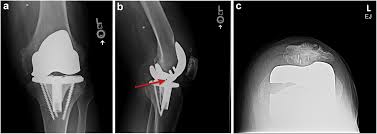

The radiographs demonstrated abnormal contour of the medial femoral condyle, consistent with an osteochondral defect, and a fabella posterior to the knee.

Palpable to either side of the knee joint when it is bent, they are known specifically as the medial and lateral femoral condyles. Sagittal plane fracture of the medial femoral condyle. Damage may also be the result of a direct blow to the knee. The flap is marked by identifying the vascular plexus on the medial condyle and incorporating a component of the network in the flap. Medial femoral condyle fracture study results.

Of the six patients who had suffered an isolated fracture of their medial condyle, four of the patients had their fractures diagnosed on the first visit. The lateral condyle was involved in 44 % and the medial condyle in 12 %. It acts to support a significant amount of the patient's body weight. Cartilage can be focally damaged, producing a pot hole in the joint surface, when the knee ligaments are injured. Osteonecrosis of the medial femoral condyle presents as a sudden onset of pain on the medial side of the knee. A bone fracture at this location is termed a femoral condyle fracture. The femoral condyle is a thickened area of the femur just above the knee. One presumed mechanism of injury is a stieda fracture (avulsion injury of the medial collateral ligament at the medial femoral condyle). Root tear (radial tear) of the medial meniscus mild or moderate knee arthritis Coronal plane fracture of the lateral femoral condyle. The lesions were located on the medial femoral condyle in 8 (72.7%) cases and on the medial tibial plateau in 3 cases (27.3%). The medial femoral condyles are the bony protrusions on the inside edge of the bottom of the femur bone in each thigh. Based on the patient's antalgic gait and radiographic findings, the patient was instructed on the proper use of crutches and referred to an orthopaedic surgeon for appropriate management.

The lateral condyle was involved in 44 % and the medial condyle in 12 %. The flap is marked by identifying the vascular plexus on the medial condyle and incorporating a component of the network in the flap. This is associated with a positive bone scan and, frequently, a radiolucent lesion in the subchondral zone. If there is a fracture (break) in part of the condyle, this is known as a fracture of the femoral condyle. Medial condyle of femur from wikipedia, the free encyclopedia the medial condyle is one of the two projections on the lower extremity of femur, the other being the lateral condyle.